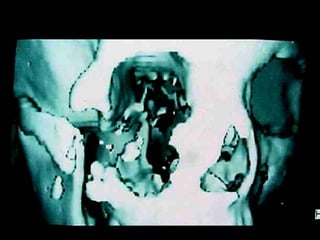

Queratoquiste odontogénico

Queratoquiste